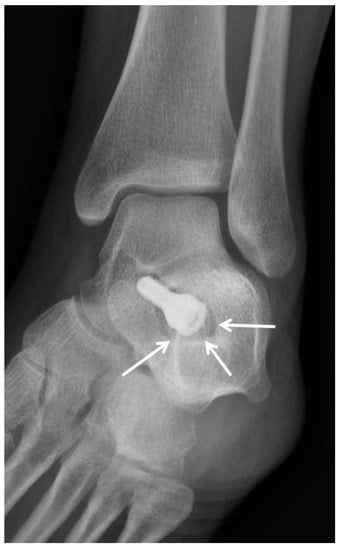

5.3. Subtalar Arthroereisis